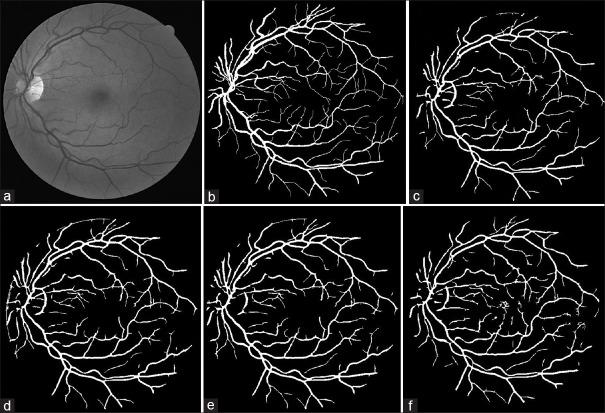

To investigate the effect of preprocessing techniques including contrast enhancement and illumination correction on retinal image quality, a comparative study was carried out. We studied and implemented a few illumination correction and contrast enhancement techniques on color retinal images to find out the best technique for optimum image enhancement. To compare and choose the best illumination correction technique we analyzed the corrected red and green components of color retinal images statistically and visually. The two contrast enhancement techniques were analyzed using a vessel segmentation algorithm by calculating the sensitivity and specificity. The statistical evaluation of the illumination correction techniques were carried out by calculating the coefficients of variation. The dividing method using the median filter to estimate background illumination showed the lowest Coefficients of variations in the red component. The quotient and homomorphic filtering methods after the dividing method presented good results based on their low Coefficients of variations. The contrast limited adaptive histogram equalization increased the sensitivity of the vessel segmentation algorithm up to 5% in the same amount of accuracy. The contrast limited adaptive histogram equalization technique has a higher sensitivity than the polynomial transformation operator as a contrast enhancement technique for vessel segmentation. Three techniques including the dividing method using the median filter to estimate background, quotient based and homomorphic filtering were found as the effective illumination correction techniques based on a statistical evaluation. Applying the local contrast enhancement technique, such as CLAHE, for fundus images presented good potentials in enhancing the vasculature segmentation.

为了研究包括对比度增强和光照校正在内的预处理技术对视网膜图像质量的影响,开展了一项对比研究。我们研究并在彩色视网膜图像上实现了几种光照校正和对比度增强技术,以找出实现最佳图像增强效果的最佳技术。为了比较并选择最佳的光照校正技术,我们对彩色视网膜图像校正后的红色和绿色分量进行了统计分析和视觉分析。通过计算灵敏度和特异性,利用血管分割算法对两种对比度增强技术进行了分析。通过计算变异系数对光照校正技术进行了统计评估。使用中值滤波器估计背景光照的划分方法在红色分量中显示出最低的变异系数。划分方法之后的商值法和同态滤波法基于其较低的变异系数呈现出良好的效果。在相同的精度下,对比度受限自适应直方图均衡化使血管分割算法的灵敏度提高了5%。作为血管分割的对比度增强技术,对比度受限自适应直方图均衡化技术比多项式变换算子具有更高的灵敏度。基于统计评估,发现包括使用中值滤波器估计背景的划分方法、商值法和同态滤波法在内的三种技术是有效的光照校正技术。将局部对比度增强技术(如对比度受限自适应直方图均衡化)应用于眼底图像在增强血管分割方面具有良好的潜力。